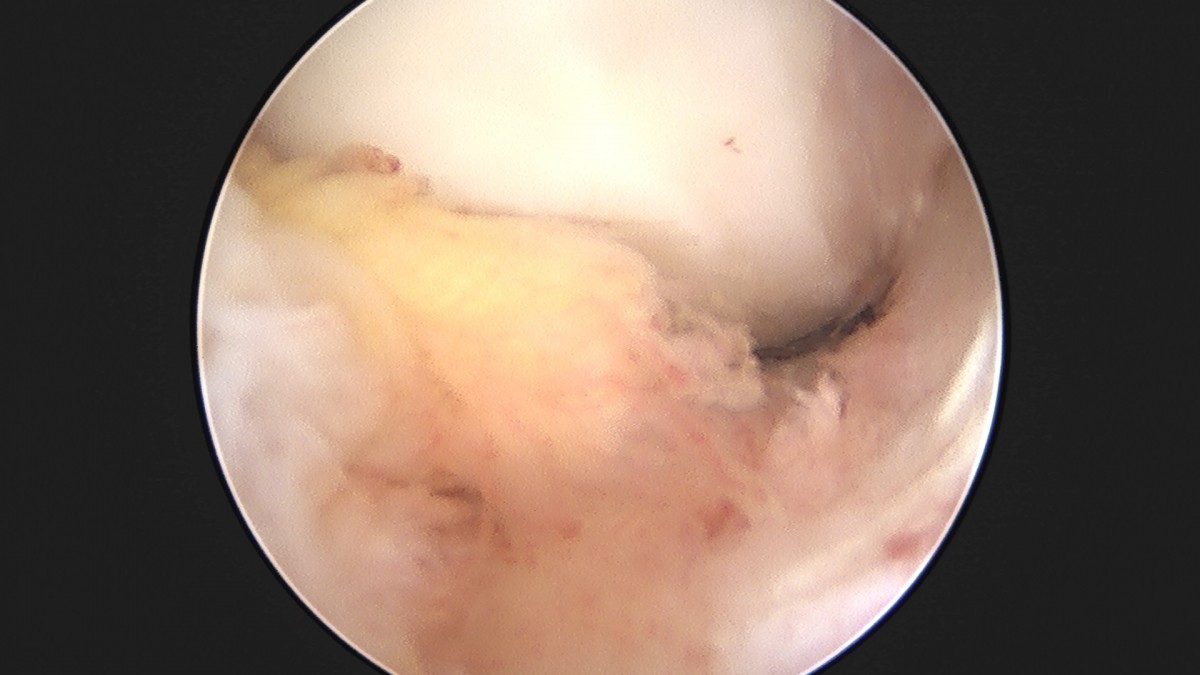

이재상원장님 무릎 반월상 연골판 절제술 박민O 환자

dae765e4d9ac96aee867c9d6292d8784_1758005185_8672.jpg